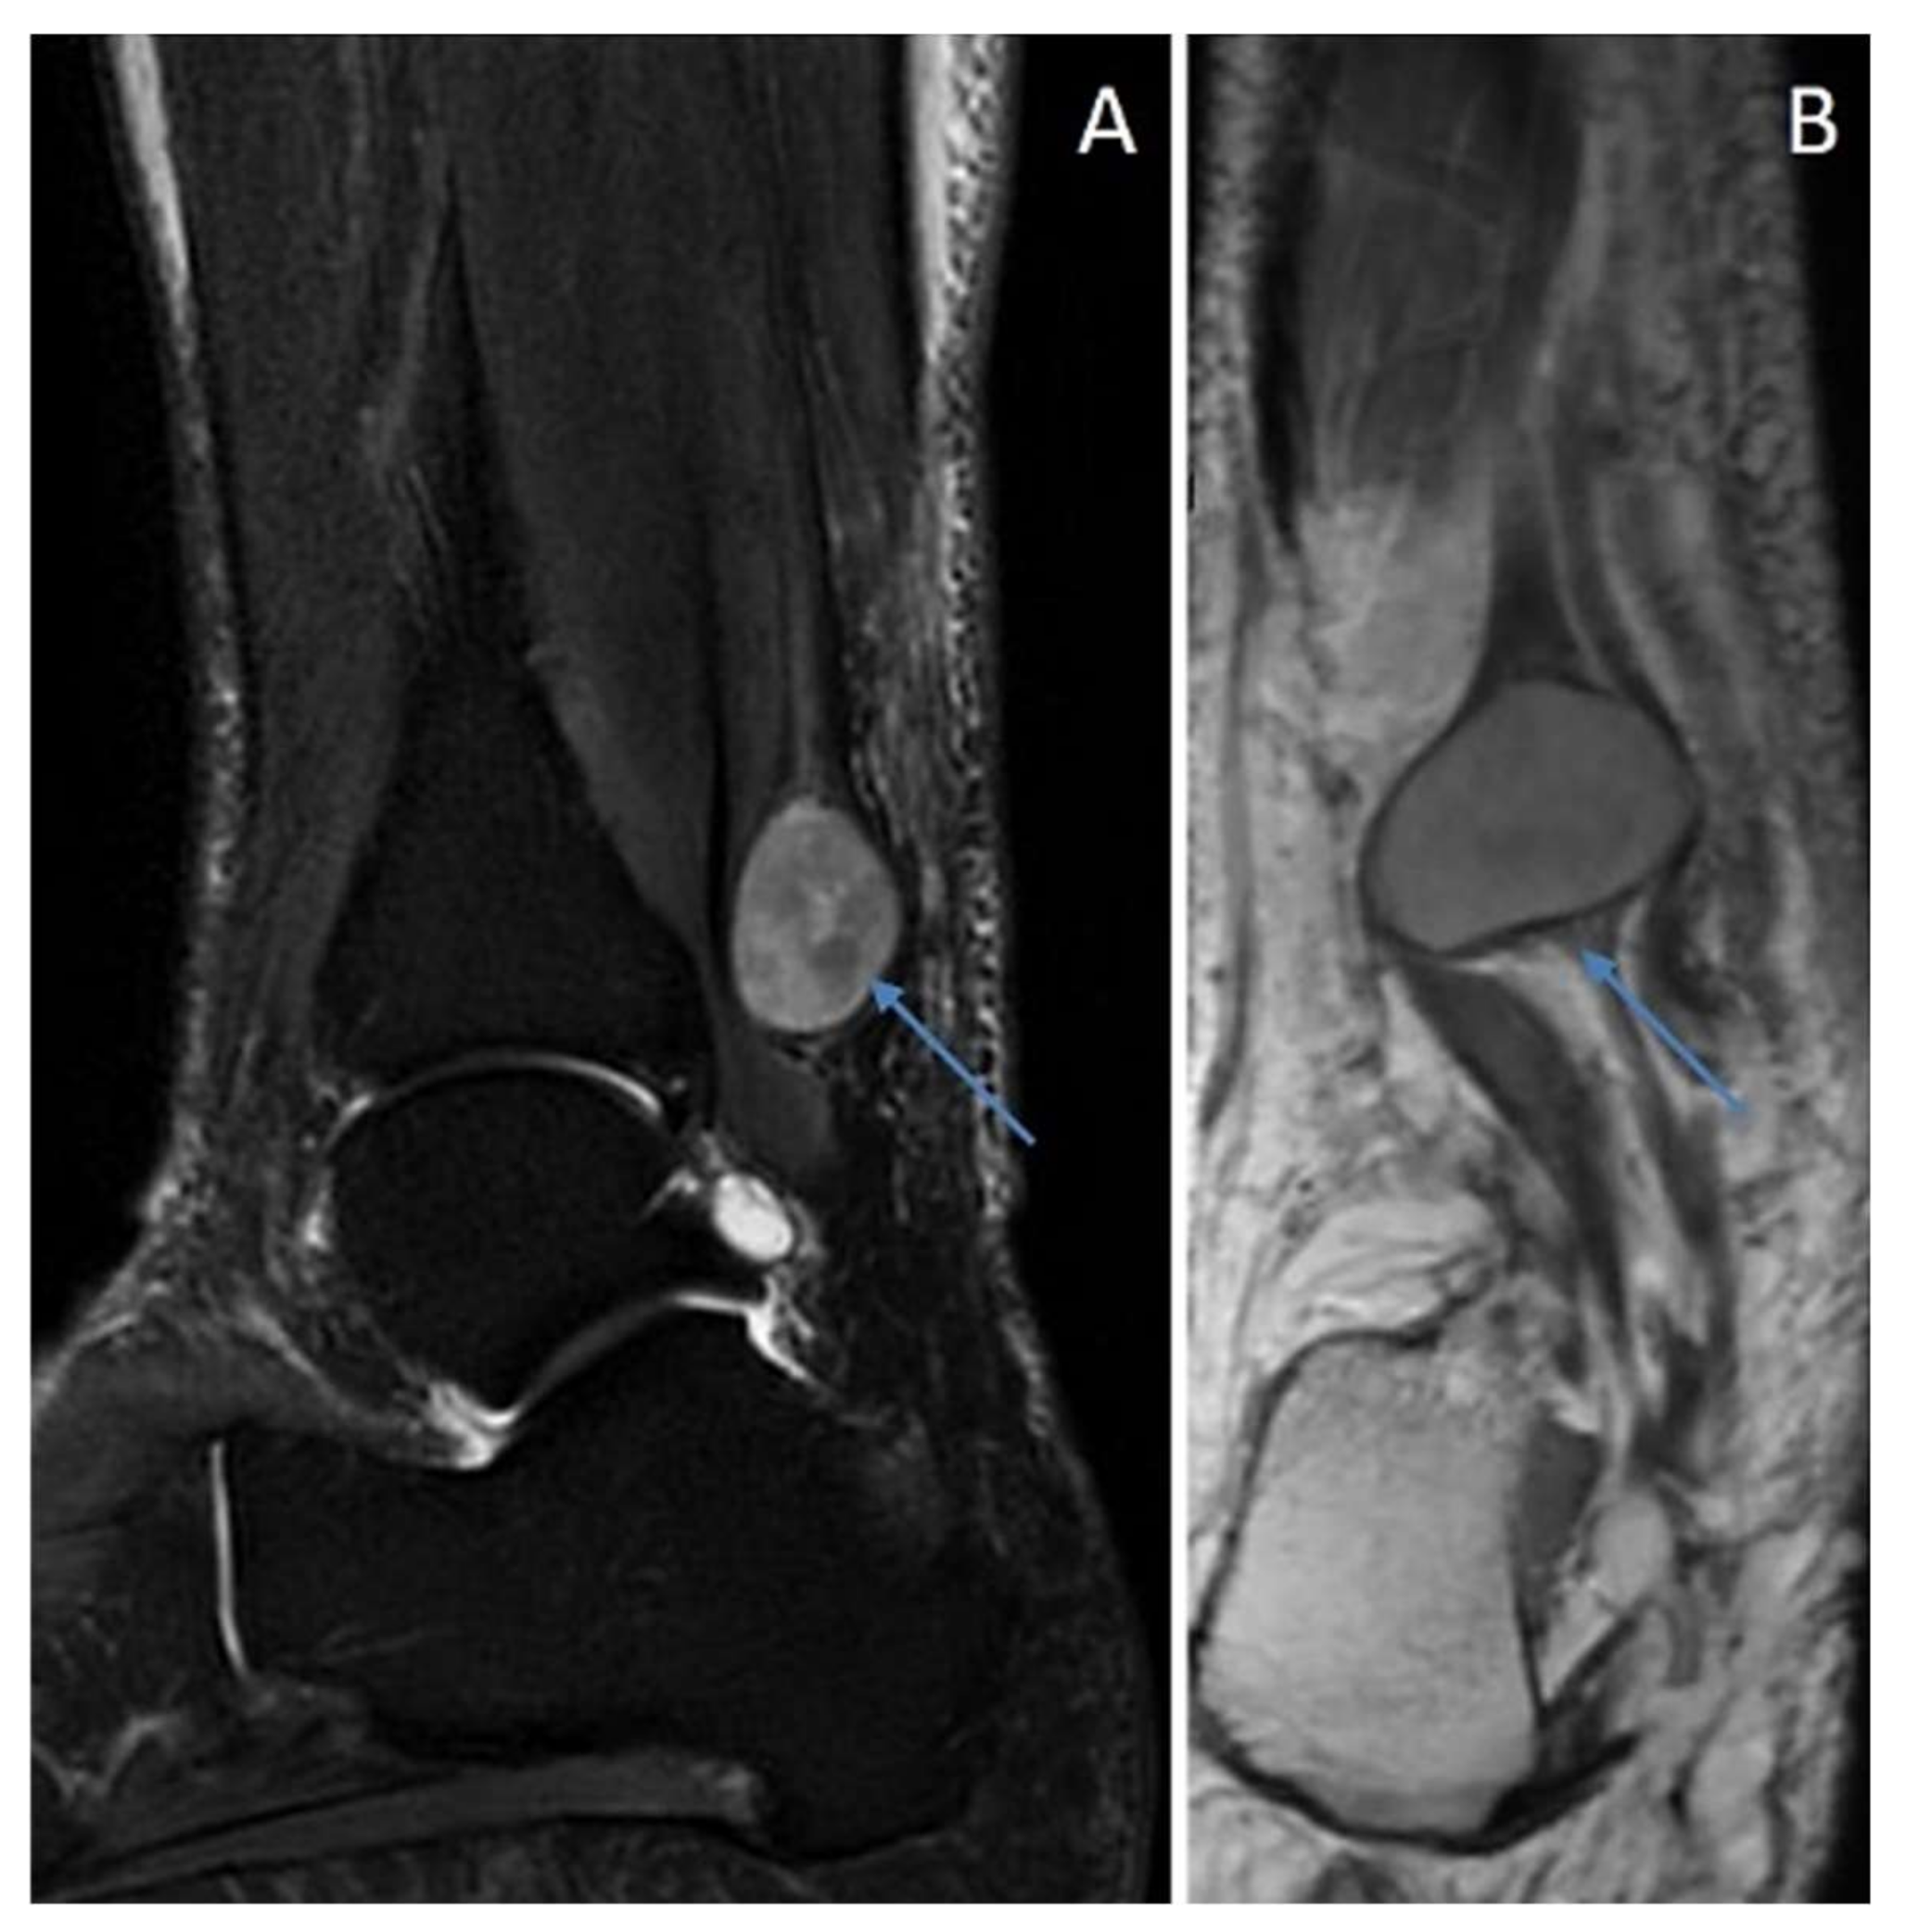

6.2. Schwannoma with Degenerative/Ancient Changes (“Ancient Schwannoma”)